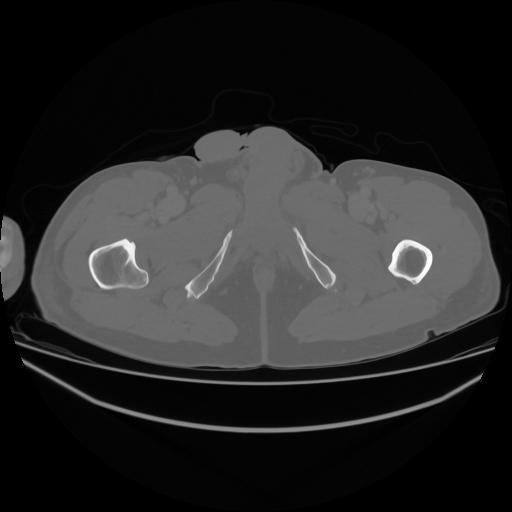

5 CUERPO,CE,Vol,1.0,CUERPO,,